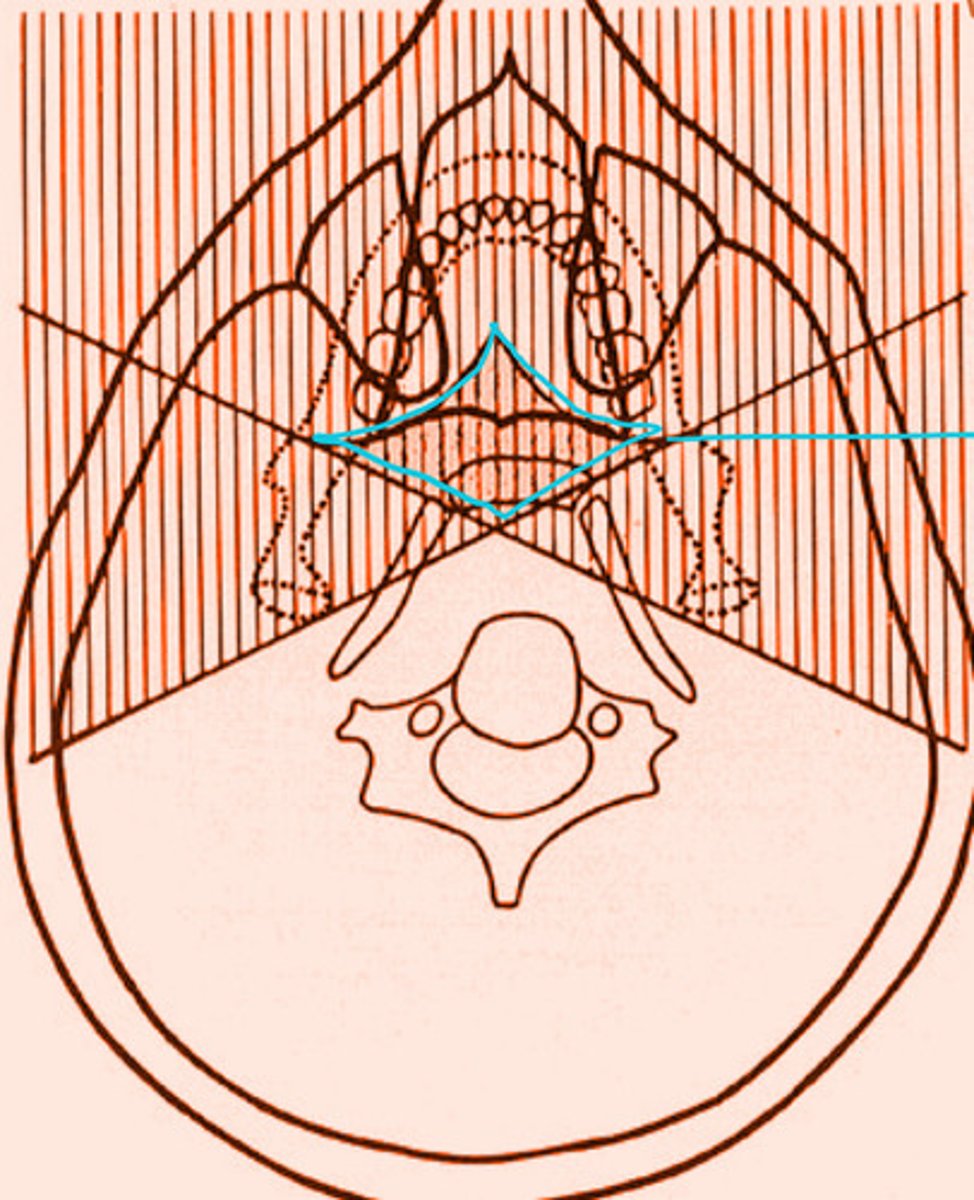

the shaded regions will produce what type of images?

real and double image

ghost image/shadows

the shaded region within the blue diamond will produce a total of __ images

3

the shaded region within the blue diamond will produce a total of 3 images. What types of images are they?

2 real

1 ghost